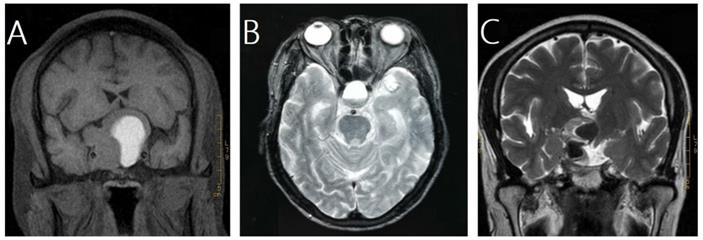

In this study, pituitary hemorrhage was diagnosed according to magnetic resonance imaging (MRI), computed tomography (CT), surgical findings or pathological findings. All of patients had MRI of sellar before and after GKRS. Images were reviewed by an experienced radiologist to confirm pituitary hemorrhage. The diagnosis of pituitary hemorrhage in MRI findings was mainly based on the following signs [21-23]: (1) hyper intense signal on T1-weighted images (acute-subacute phase, Fig. 1A), (2) a fluid-fluid level in the mass (chronic phase, Fig. 1B), (3) very low intensity of hemosiderin on T2-weighted images (chronic phase, Fig. 1C).

Magnetic resonance images of three cases of pituitary hemorrhage. A, a 43-year-old male with nonfunctioning pituitary adenoma (NFPA) presenting as a high intensity area on a coronal T1-weighted image. B, a 69-year-old male with NFPA showing the sign of a fluid-fluid level on an axial T2-weighted image. C, a 47-year-old male with NFPA presenting as a very low intensity area on a coronal T2-weighted image.